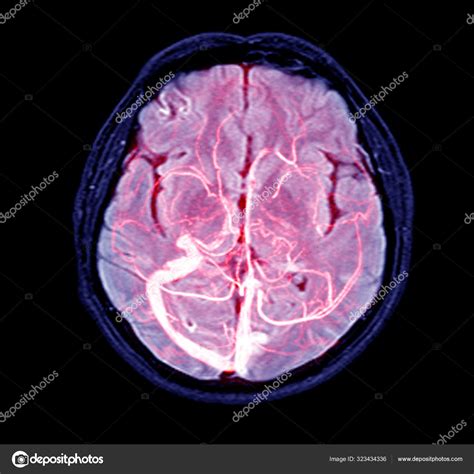

The core technology behind an MRV is the same as a standard MRI machine—a large tube surrounded by a powerful circular magnet. For an MRV, the process is often enhanced with the use of a gadolinium-based contrast agent. This contrast dye is injected into a vein in your arm, which helps the blood vessels "light up" on the resulting images, providing a clear contrast between the vessels and the surrounding brain tissue.

The imaging machine detects the signals emitted by the blood flow within these enhanced vessels, creating a high-resolution map of the venous drainage system. The entire process is non-invasive, meaning no surgical intervention is required.